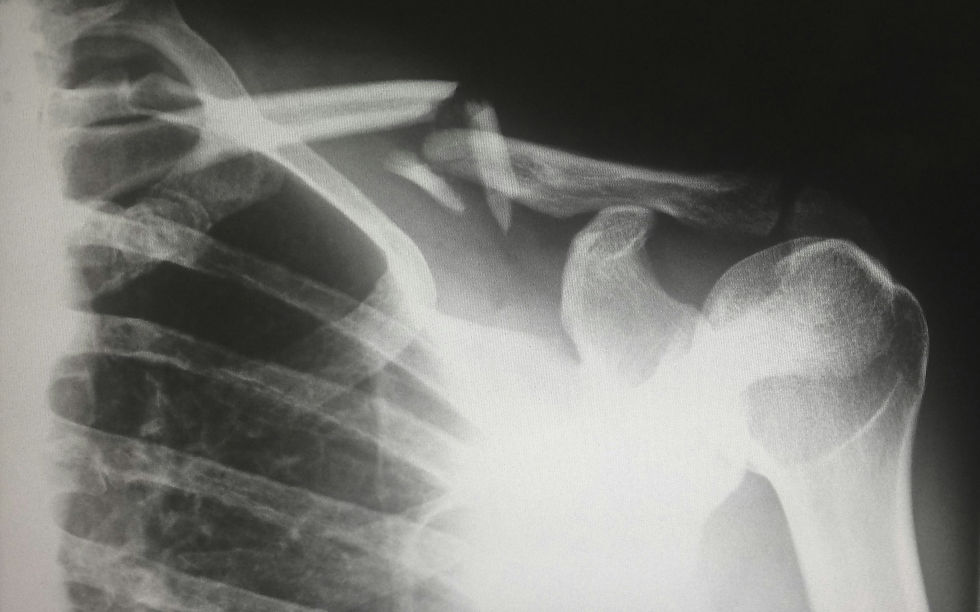

The shoulder complex, says Severe, is complex. “It’s an enigma. Even though we say the shoulder hasn’t change since we stood upright, you just need to know the structures and how they function. You can look at a normal shoulder, hundreds of shoulders, but until you see one that doesn’t function normally, it’s a whole different ball of wax. It’s something we always want to learn about.”

“If somebody doesn’t have an active serratus, their scapula doesn’t move, right?” says Severe. “It doesn’t sit on the thoracic wall to be able to support the structure of the arm to be able to lift and move. So we have to figure out how to compensate for that and help facilitate strength.”